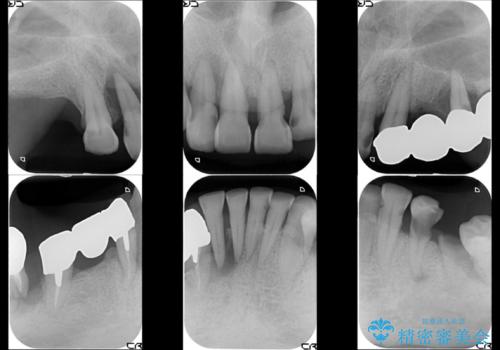

虫歯だらけ、歯周病 崩壊した口腔の再建 フルマウスリコンストラクション

- 歯周外科・インプラント・顕微鏡下根管治療などを含んだ総合的な治療を計画した。

かみ合わせの力が非常に強く、夜間の歯ぎしり・食いしばりもひどかったため、奥歯はメタルオクルーザルの設計でかぶせ物を製作しています。